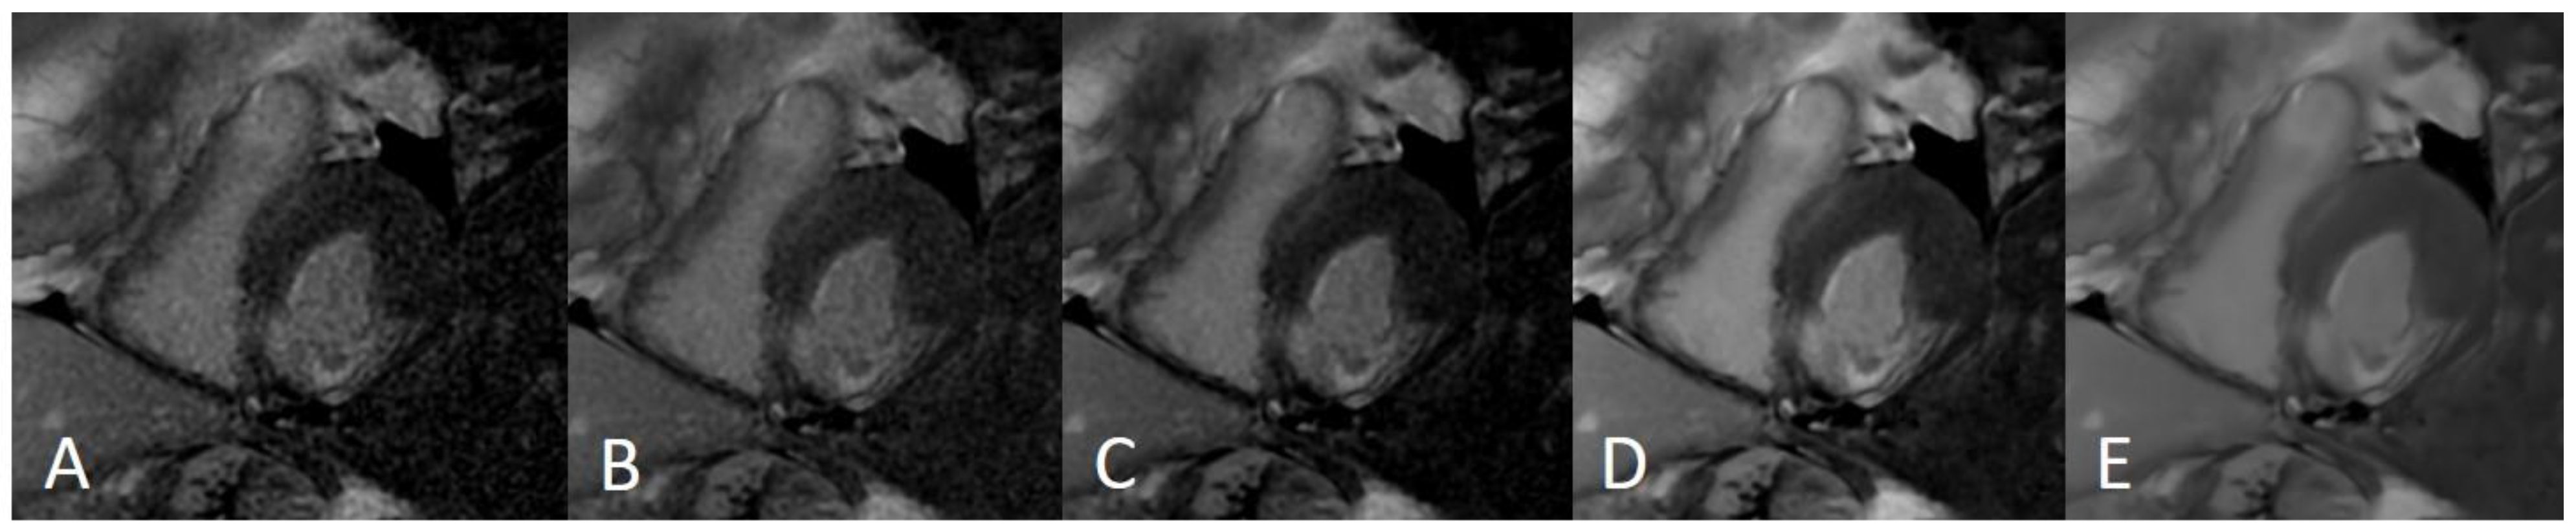

Figure 4.

LGE —late gadolinium enhancement sequences acquired using the compressed sensing technique. Panel (A)—Left ventricle (LV) and right ventricle (RV) short axis view at the level pf the papillary muscles; (B)—LV three chamber view; (C)—LV two chamber view; (D)—LV and RV four chamber view.